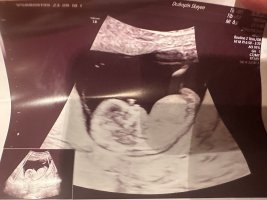

Tipper guttNoen som klarer tyde nub her? 12+5

Skal jeg tippe, ville jeg sagt jenteNoen som kan se noe her?